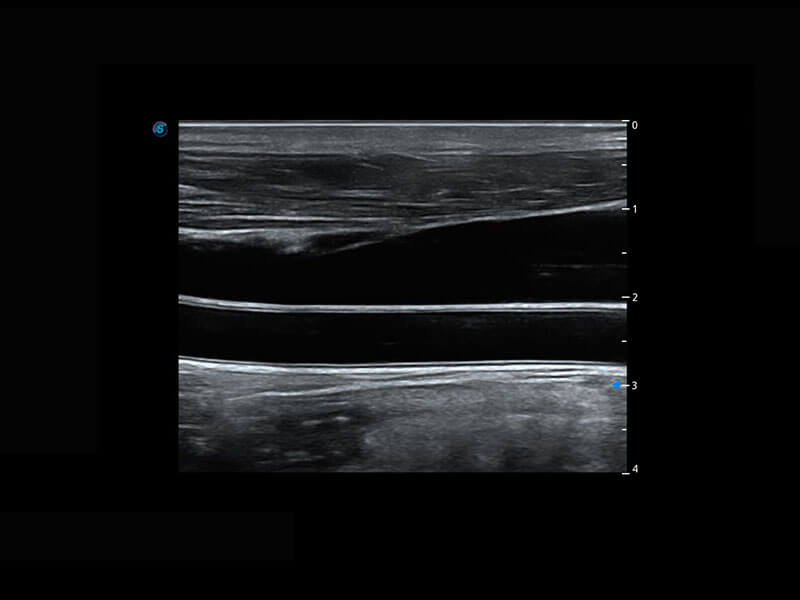

P60搭載寬頻帶線(xiàn)陣探頭、寬景成像、彈性成像技術(shù),為您提供乳腺應(yīng)用方案。P60支持高頻相控陣探頭、線(xiàn)陣探頭、腹部高頻探頭、腹部微凸探頭等,豐富的探頭群搭載敏感的彩色血流成像,適用于新生兒多種臟器檢測(cè)要求,滿(mǎn)足新生兒篩查需求。